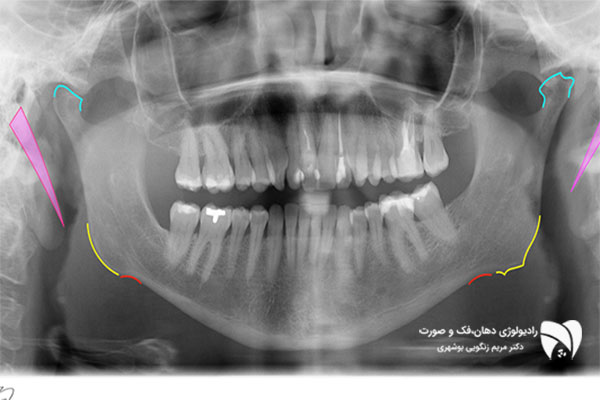

رادیولوژی دهان، علمی است که به تصویربرداری دهان، فک و صورت با استفاده از تکنولوژی پرتونگاری می‌پردازد. این تصاویر به دندانپزشکان کمک می‌کنند تا بیماری‌های دهانی را شناسایی کرده و روش‌های درمانی را برای آنها برنامه‌ریزی کنند.

از جمله بیماری‌هایی که با استفاده از تصویر برداری دهان قابل شناسایی می‌باشند، می‌توان به پوسیدگی دندان ها،  التهاب استخون و بافت های نگهدارنده دندان، عفونت دندان ها و بافت های اطراف آن ها، وجود شکستگی در دندان ها و استخوان های فکین، تومورهای دهان و فک و صورت و … اشاره کرد.

علاوه بر این، رادیولوژی دهان در بررسی مسائل مربوط به مفاصل فک و بافت‌های نرم صورت در شرایط خاص  نیز مورد استفاده قرار می‌گیرد.